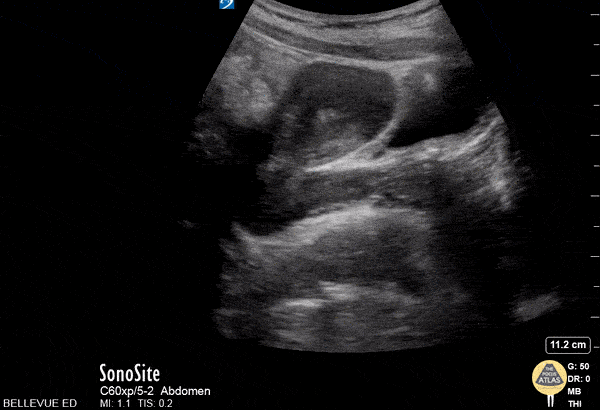

OB/Gyn - Transabdominal Uterus Long Axis

This is a transabdominal image of the uterus in long (sagittal) axis. On the far right of the screen we see the anechoic urine filled bladder. Immediately to the left of the bladder is the anteverted uterus which can be followed down and to the right as it curves and transitions into cervix and vagina. The thin, hyperechoic line in the center of the uterus is the endometrial stripe. Hannah Kopinksi and Dr. Lindsay Davis - NYU Emergency Medicine